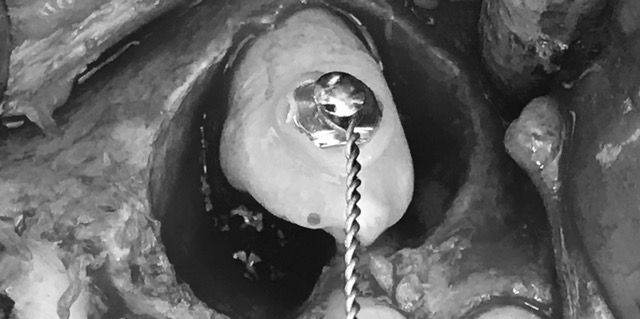

Rimozione della cisti e agganciamento del canino